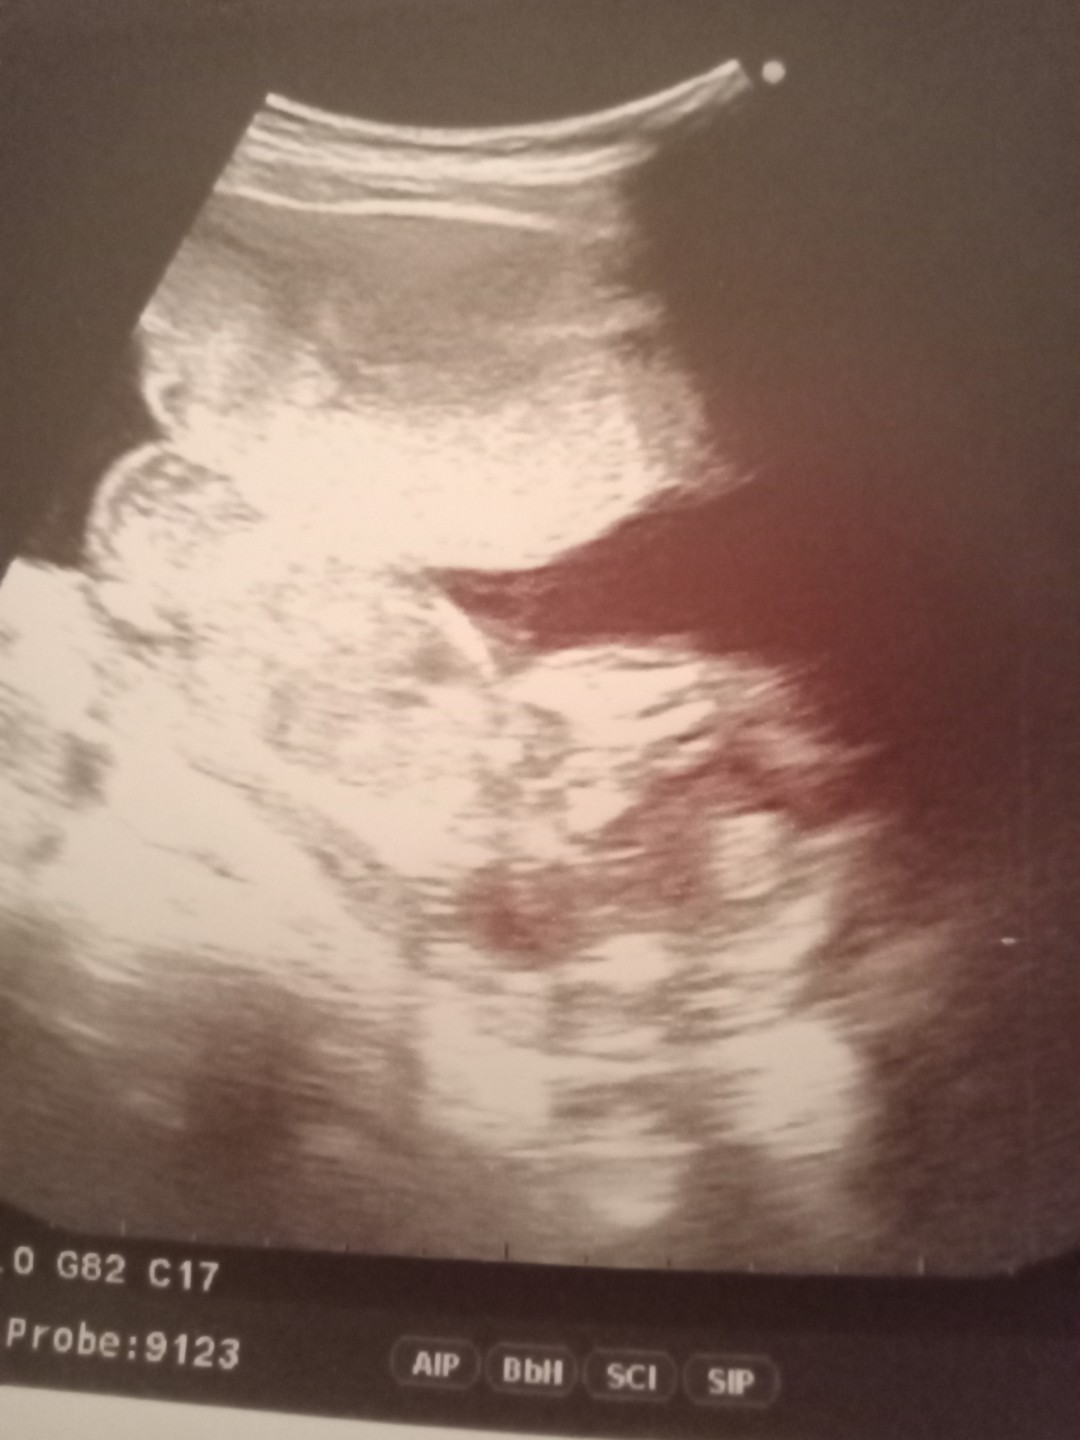

32+6แล้วจ้า ผู้ชาย 2100กรัม ปวดร้าวช่วงล่างมากจ้า